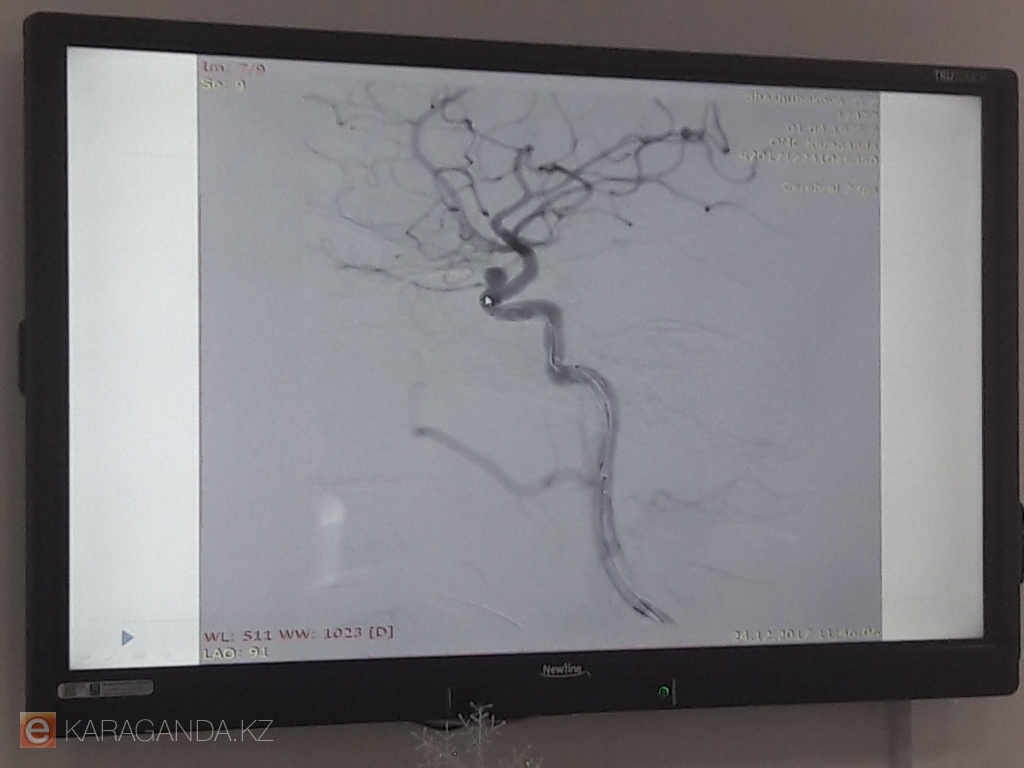

1 марта 2017 года на базе КГП «ОМЦ» был открыт Центр нейрохирургии и неврологии, в составе которого функционируют: отделение плановой нейрохирургии, отделение экстренной нейрохирургии, инсультное отделение, отделение неврологии, отделение продолженной реабилитации, то есть полный цикл стационарного лечения пациентов неврологического и нейрохирургического профилей.

Одно из новых видов оборудования, которое работает во благо карагандинцев - это ангиографическая система. Новое оборудование в формате 3D позволяет хирургам качественно установить стент в сосуды. Это позволяет лечить пациентов уже сразу после определения диагноза, а также выписывать их в течение трех дней после операции.

- Новые технологии позволяют видеть работу в точнейшей графике, - говорит , - Габит Махамбаев, главный нейрохирург карагандинской области. - Аппарат аниографической системы поступил уже к нам, наши сотрудники прошли специальные курсы подготовки. На этом мы не будем останавливаться, а продолжим работу, ведь данный аппарат позволяет проводить многие виды операций.